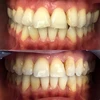

Zirkonyum uygulamalar

Porselen uygulamaları

Laminate veneer